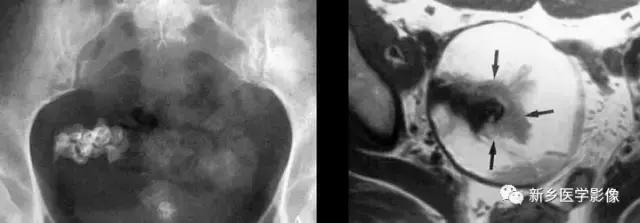

卵巢肿瘤畸胎瘤

常见的为畸胎瘤以及合并钙化的卵巢癌